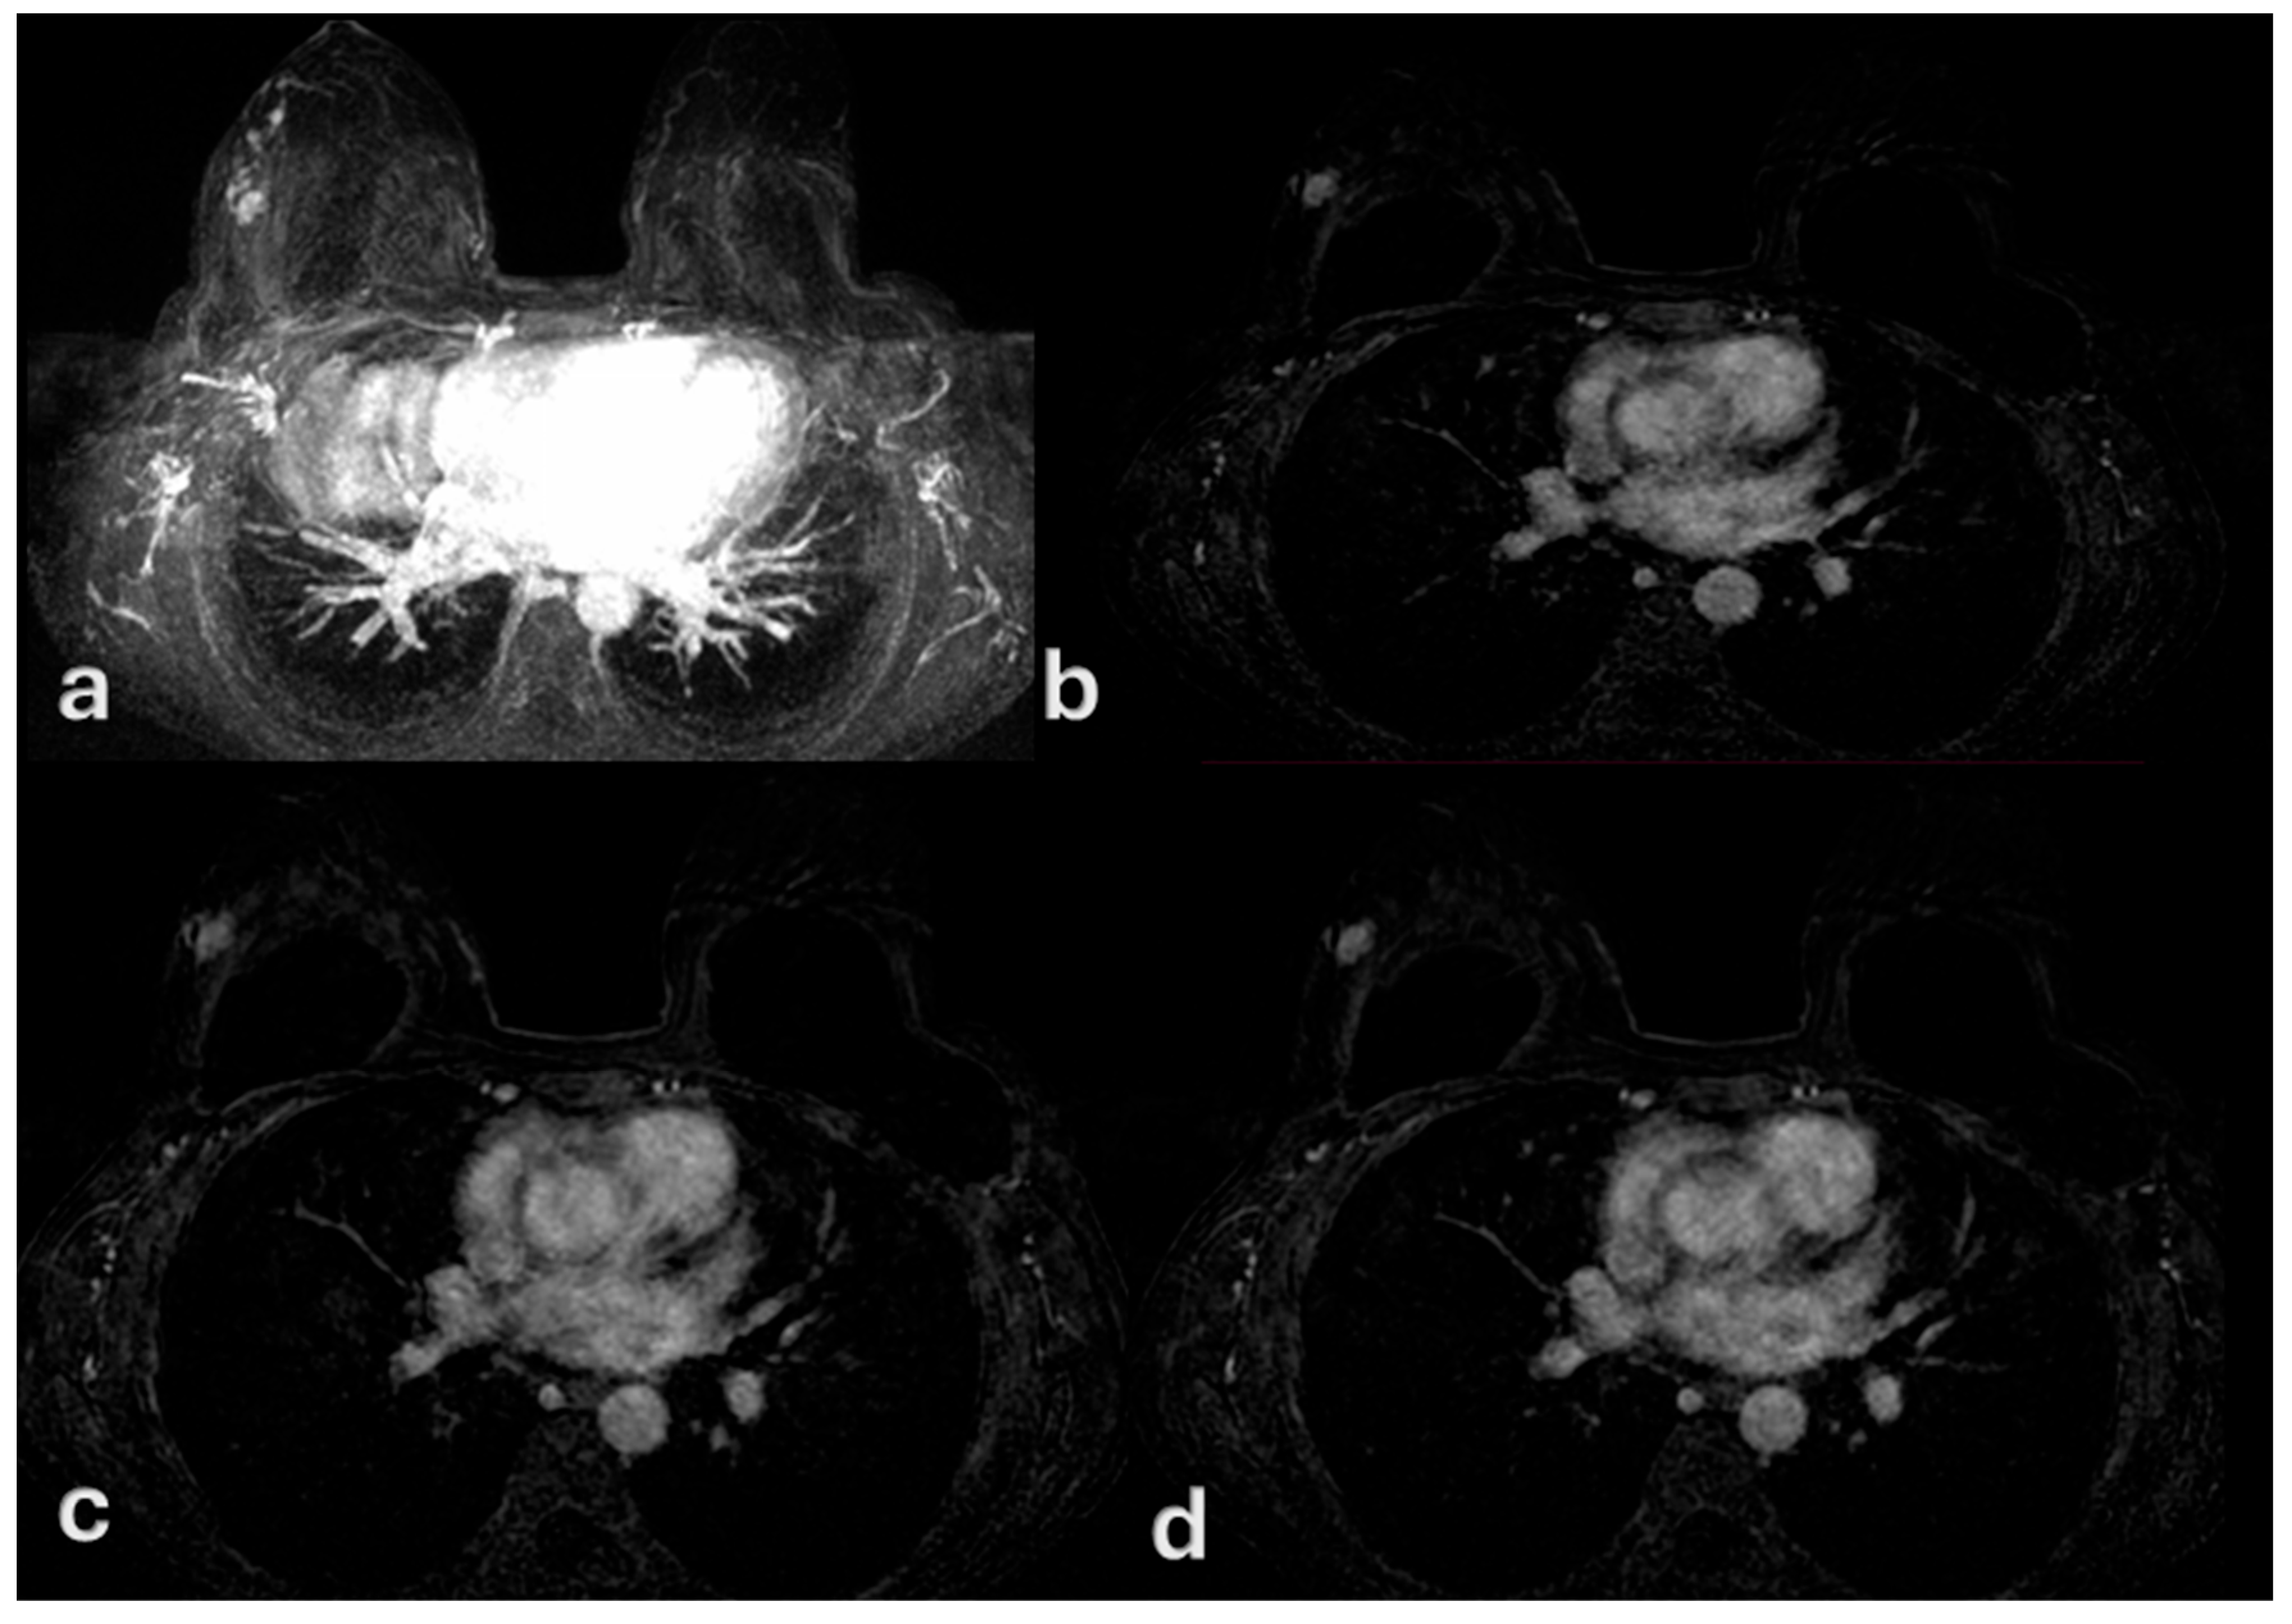

- Benveniste, A.P.; Ortiz-Perez, T.; Ebuoma, L.O.; Sepulveda, K.A.; Severs, F.J.; Roark, A.; Wang, T.; Sedgwick, E.L. Is breast magnetic resonance imaging (MRI) useful for diagnosis of additional sites of disease in patients recently diagnosed with pure ductal carcinoma in situ (DCIS)? Eur. J. Radiol. 2017, 96, 74–79. [Google Scholar] [CrossRef]

- Esserman, L.J.; Kumar, A.S.; Herrera, A.F.; Leung, J.; Au, A.; Chen, Y.Y.; Moore, D.H.; Chen, D.F.; Hellawell, J.; Wolverton, D.; et al. Magnetic resonance imaging captures the biology of ductal carcinoma in situ. J. Clin. Oncol. 2006, 24, 4603–4610. [Google Scholar] [CrossRef]

- Viehweg, P.; Lampe, D.; Buchmann, J.; Heywang-Köbrunner, S.H. In situ and minimally invasive breast cancer: Morphologic and kinetic features on contrast-enhanced MR imaging. Magn. Reson. Mater. Phys. Biol. Med. 2000, 11, 129–137. [Google Scholar] [CrossRef]

- Chan, S.; Chen, J.H.; Agrawal, G.; Lin, M.; Mehta, R.S.; Carpenter, P.M.; Nalcioglu, O.; Su, M.Y. Characterization of Pure Ductal Carcinoma In Situ on Dynamic Contrast-Enhanced MR Imaging: Do Nonhigh Grade and High Grade Show Different Imaging Features? J. Oncol. 2010, 2010, 431341. [Google Scholar] [CrossRef]